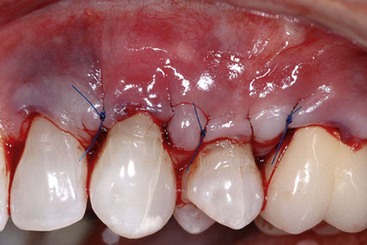

image

Supplement A Figure 63-4 AlloDerm sutured within the pouch.